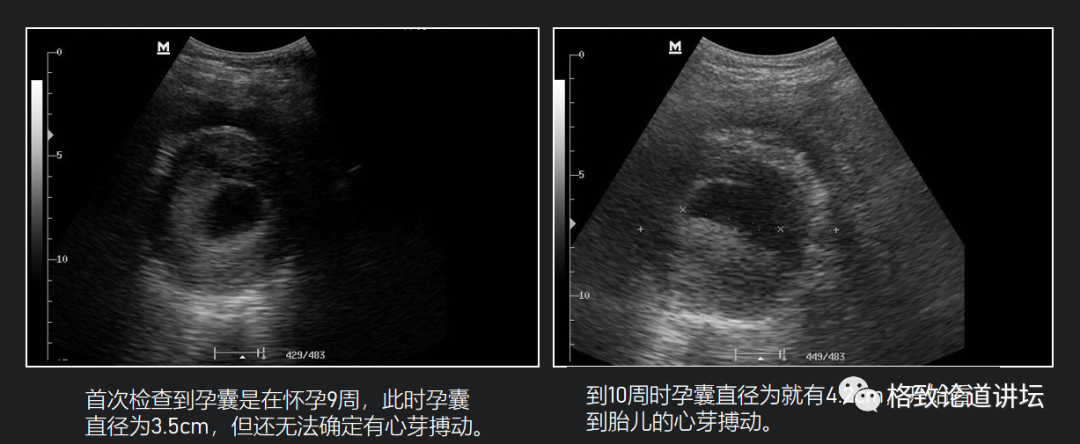

下面这是我们的黑猩猩小珊怀孕了。我们在第九周的时候给它做B超,发现了孕囊,但是还没有测到胎儿的心跳。我们在第十周的时候测到了胎儿的心跳,我们的团队非常激动,高兴得像有了自己的孩子,同时也是喜忧参半的。喜的是一个新的生命孕育了,忧的是不知道这个孩子能不能顺利地、健康地生出来。

所以在小珊的整个孕期中,我们用B超去监测胎儿的发育和健康。我们不仅监测它的发育速度,而且还监测是否存在脐带绕颈、胎位不正的问题,同时监测胎盘的成熟度去预测预产期。

黑猩猩小珊的孕期B超

在第33周的时候,小珊顺利生下了一个健康的男宝宝。因为它的眼睛乌黑亮丽,它的辈分又是豆字辈的,所以我们给它起了个名字叫乌豆。